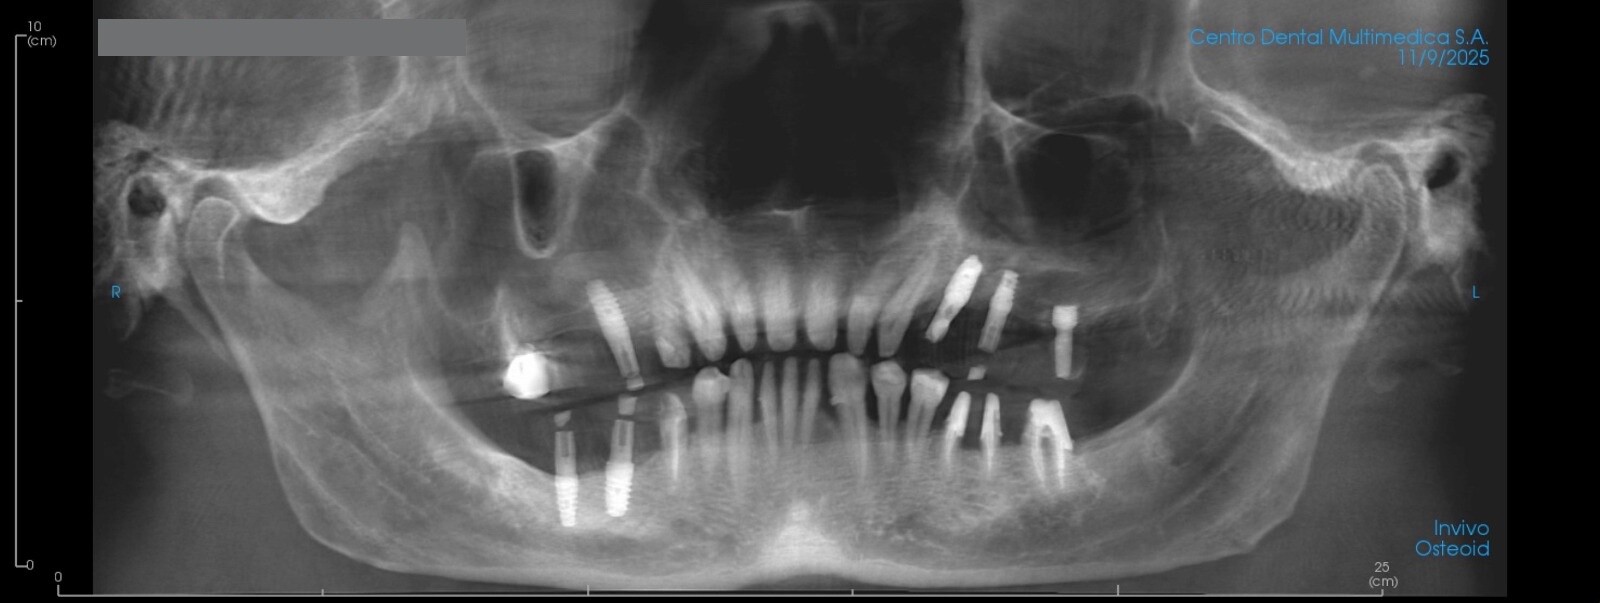

Reconstrucción digital de una tomografía dental en formato de 12 x 18.

La radiografía digital tridimensional (CBCT) aporta información volumétrica ósea indispensable para la planificación implantológica, quirúrgica y ortodóncica avanzada. Su integración con modelos digitales permite una evaluación tridimensional más precisa de las relaciones anatómicas5.

Radiografía panorámica hecha de una reconstrucción de una tomografía dental.